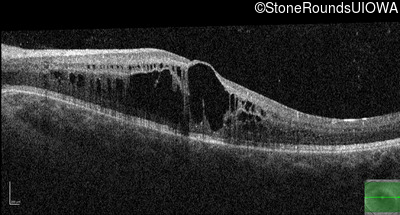

Optical Coherence Tomography - Left - 20/50 -2

Exemplar / OCT Stack

OCT Stack